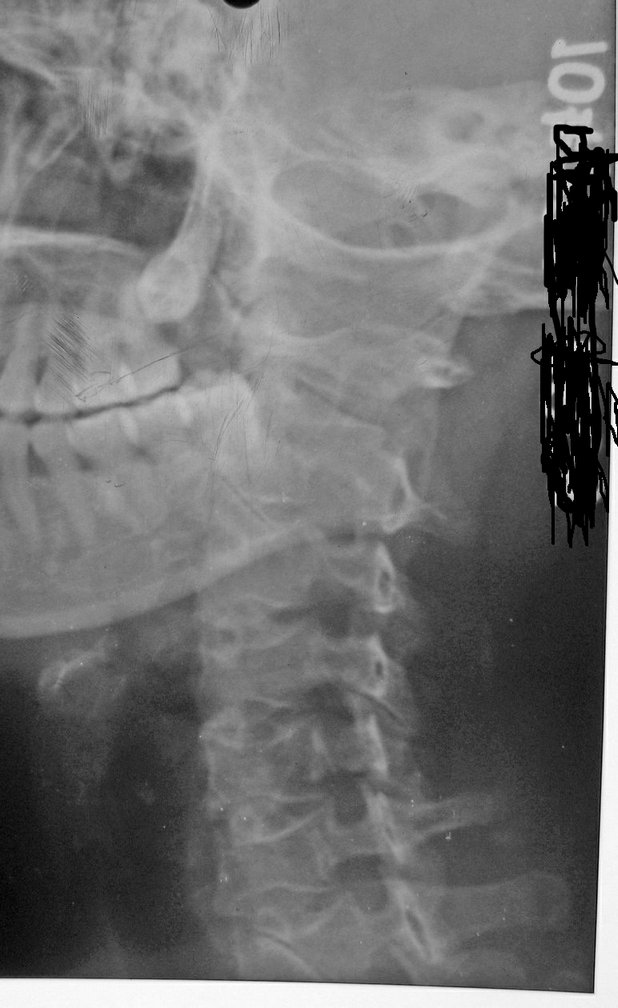

以下是引用拾荒者在2010-7-5 21:08:00的发言:[br]1.膝关节退行性变;2.颈椎未见明显异常。

以下是引用hexue在2010-7-5 22:47:00的发言:[br]1.膝关节退行性变;2.颈椎未见明显异常。 [br] [br]

以下是引用随光逐影在2010-7-6 7:11:00的发言:[br]病例1:双膝关节退行性骨关节病。[br]病例2:1)颈椎未见明确异常。2)一侧下颌智齿横位阻生。